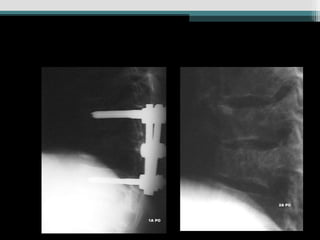

Caso 1 (34anos, queda, Fk e)

• 62.

Caso 2 (25anos, auto, Fk a) www.traumatologiaeortopedia.com.b